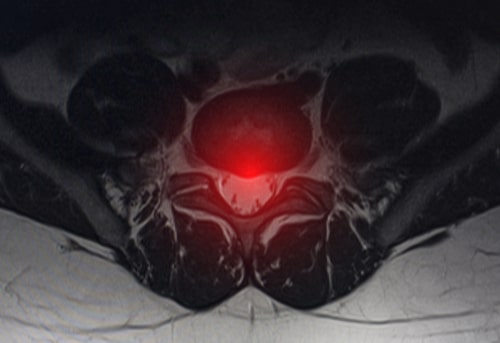

Imagina el disco intervertebral como un cojín entre las vértebras de nuestra columna vertebral. Está compuesto por una parte externa llamada anillo fibroso y una parte interna gelatinosa llamada núcleo pulposo.

Este disco actúa como un amortiguador que ayuda a absorber los impactos y proporciona flexibilidad a nuestra columna vertebral. Es importante que sepas que en el interior de un disco intervertebral sano no hay vasos ni terminaciones nerviosas. por tanto el disco es avascular y las terminaciones nerviosas se encuentran en la periferia del anillo fibroso.

Una vez roto el anillo discal puede ocurrir que el contenido del núcleo pulposo salga del interior del disco y se produzca una hernia.